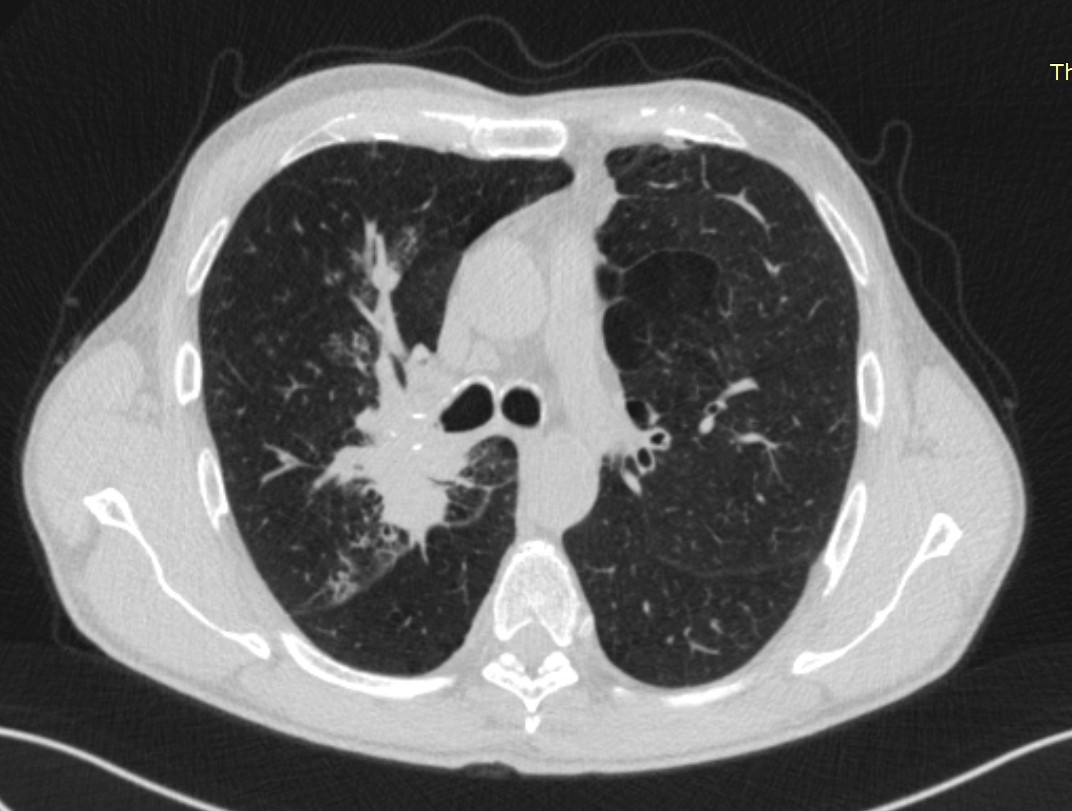

- გულმკერდის კტ აქსიალურ ჭრილში 2 თვით ადრე